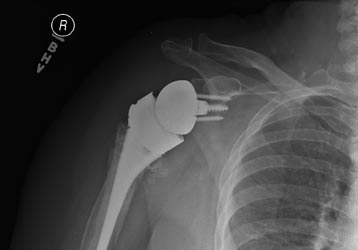

Reverse Shoulder Replacement for Non-united Fracture